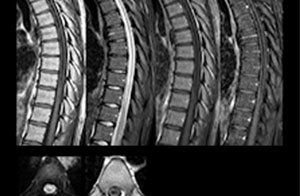

“We use mDIXON TSE extensively in our spine imaging in the emergency room,” says Dr. Karis. “It’s particularly nice in that it is very robust with regard to susceptibility type of problems that would come up with traditional spectral fat-saturated images; these problems are essentially eliminated with the mDIXON technique. In our ED environment it’s really nice to have the fat-free imaging that goes along with the mDIXON technique.

“For the thoracic and cervical spine routine non-contrast exam, for example, we perform one mDIXON T2 TSE sequence, which provides us with two outputs: the fat-and-water-together T2-weighted images, as well as the water-only sagittal T2-weighted images. And then we also perform an axial gradient echo exam.”

To minimize the time taken to perform scans, rapid MRI examination protocols (ExamCards) were developed, shortening the total scanning time to even less than 10 minutes in some exams. Techniques like mDIXON (modified DIXON) are used for robust capturing of fat-free MRI images in a hectic ED environment.

in image acquisition and postprocessing algorithms.”“mDIXON TSE sequences allow simultaneous characterization of morphological changes from the in-phase T2-weighted images and visualization of edematous changes, thanks to the water T2-weighted images from the same acquisition. Anatomical and morphological considerations could be a partial or complete ligament tear, a bony avulsion or hematoma.”

“mDIXON TSE sequences allow simultaneous characterization of morphological changes from the in-phase T2-weighted images and visualization of edematous changes, thanks to the water T2-weighted images from the same acquisition. Anatomical and morphological considerations could be a partial or complete ligament tear, a bony avulsion or hematoma.”